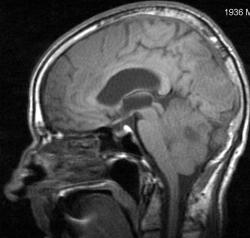

Мужчина 73 лет. За последний год похудел, потерял аппетит. Последний месяц стал плохо ходить, несколько раз падал, неделю назад стал психически не совсем адекватен. Врач - друг семьи, приехавший в гости, настоял на проведении МРТ головного мозга, рентгенографии ОГК и УЗИ брюшной полости. МРТ проводилось в медикаментозном сне, с реанимационным набором наизготовку, по немного укороченным программам. Все закончилось благополучно. Ничего сложного в плане диагностики. Просто не всегда бывает так много и ярко. Есть небольшое продолжение. Потом.

Т1 сагиттальные сканы:

метастазы